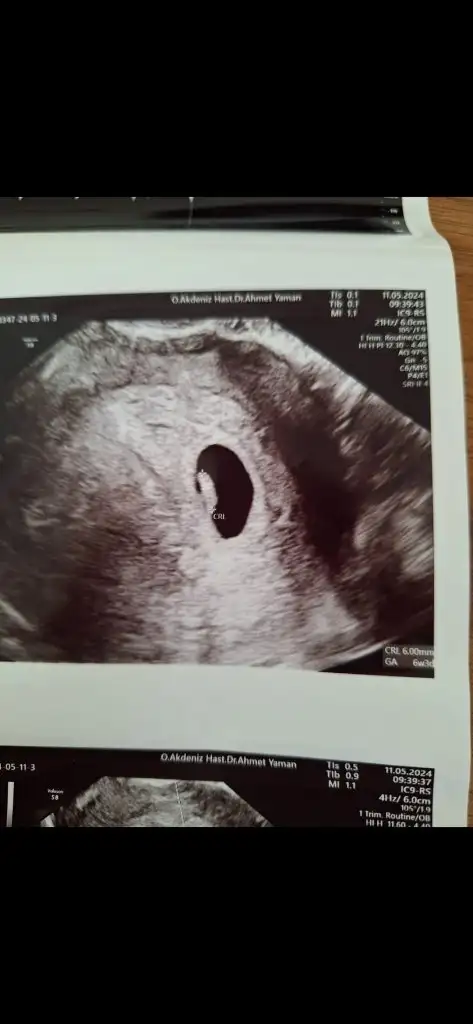

Hayırlı olsun canım benim , sağlıkla gelsin inşallah bebişinMerhaba kızlar. Sanırım bu grupta olacağım. Sat göre 8 haftalik gözüküyor ama ben de pckos olduğundan dolayı geç döllenme oldu. Hatta erken gebelik testi yaptım çift çizgiyi göremedim üzülmüştüm. 1 hafta sonra kaset test yaptım çift çizgiyi gördüm. Doktora gitmeden geç döllenme olduğunu anlamıştım. İlk 696 ile öğrendim 2 gün sonra 2798 değer ile tahminen 5 haftalikken keseyi gördük bebek yoktu. Bugün de doktorun hesaplamasına göre 6+3 hem keseyi hem kalp atışını duyduk. Sadece biraz tedirginim daha öncesinde 1 kimyasal bir de 8 haftalıkken kalbi durdu bebeğimin. Doktor önlem amaçlı progestan verdi fitil olarak ayrıca oksapar iğne verdi. Bugün de d vitamini magnezyum i mom gibi vitaminlere başlattı. Gebelikte bakılan rutin testler için kan ve idrar istedi.

Hayırlı olsun bebişinizi sağlıcakla kucağınıza alın inşallahMerhaba kızlar. Sanırım bu grupta olacağım. Sat göre 8 haftalik gözüküyor ama ben de pckos olduğundan dolayı geç döllenme oldu. Hatta erken gebelik testi yaptım çift çizgiyi göremedim üzülmüştüm. 1 hafta sonra kaset test yaptım çift çizgiyi gördüm. Doktora gitmeden geç döllenme olduğunu anlamıştım. İlk 696 ile öğrendim 2 gün sonra 2798 değer ile tahminen 5 haftalikken keseyi gördük bebek yoktu. Bugün de doktorun hesaplamasına göre 6+3 hem keseyi hem kalp atışını duyduk. Sadece biraz tedirginim daha öncesinde 1 kimyasal bir de 8 haftalıkken kalbi durdu bebeğimin. Doktor önlem amaçlı progestan verdi fitil olarak ayrıca oksapar iğne verdi. Bugün de d vitamini magnezyum i mom gibi vitaminlere başlattı. Gebelikte bakılan rutin testler için kan ve idrar istedi.